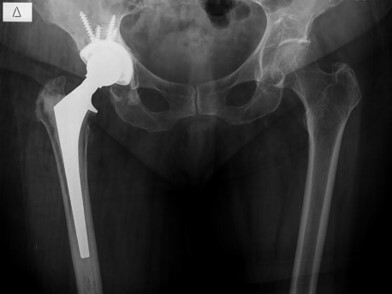

Ωστόσο, όπως και με οποιαδήποτε άλλη πρόθεση, η ολική αρθροπλαστική του ισχίου μπορεί να υποστεί διάφορες μορφές μηχανικής ή βιολογικής αποτυχίας. Μια τέτοια αποτυχία μπορεί να οδηγήσει σε μια νέα επέμβαση για την αντιμετώπιση της. Η επανεπέμβαση μετά από ολική αθροπλαστική ισχίου ονομάζεται αναθεώρηση του ισχίου.

Η δομή της πρόθεσης παρομοιάζει τη δομή του πραγματικού ισχίου με μια σφαιροειδή άρθρωση (ball and socket). Για να λειτουργήσει καλά η πρόθεση, θα πρέπει η πρόθεση του μηρού να είναι πάντα μέσα στην πρόθεση της κοτύλης. Δύο βασικοί παράγοντες για την αποφυγή του εξαρθρήματος του ισχίου είναι: ο σωστός προσανατολισμός της πρόθεσης του μηρού και της κοτύλης όπως και οι δυνάμεις που παράγονται από τους μύες και τους συνδέσμους γύρω από την άρθρωση του ισχίου.

Η ολική αρθροπλαστική του ισχίου έχει σχεδιαστεί για να παρέχει μεγάλο εύρος κίνησης. Παρόλα αυτά, ο τραυματισμός ή συγκεκριμένες θέσεις της άρθρωσης του ισχίου μπορούν να εξαναγκάσουν την πρόθεση του μηρού να βγει από την πρόθεση της κοτύλης, μία κατάσταση που ονομάζεται εξάρθρημα του ισχίου

Το εξάρθρημα είναι σχετικά σπάνιο αλλά μετα από το πρώτο επεισόδιο εξαρθρήματος του ισχίου υπάρχει αρκετά αυξημένη προδιάθεση να επαναληφθεί καθώς το εξαρθρωμένο ισχίο διαταράσσει τους μύες και τους συνδέσμους γύρω από το ισχίο. Τα πολλαπλά εξαρθρήματα σε αρθροπλαστική του ισχίου είναι σπάνιο φαινόμενο, ωστόσο μπορεί να συμβούν σε ασθενείς που έχουν υποστεί πολλαπλά εξαρθρήματα του ισχίου. Στη συγκεκριμένη περίπτωση, ο ορθοπαιδικός χειρουργός μπορεί να προτείνει την αναθεώρηση.

Σε ορισμένες περιπτώσεις, ο χειρουργός μπορεί να χρησιμοποιήσει μια συσκευή που μπορεί να περιορίζει την πρόθεση του μηρού να εξαρθρώνεται σε σχέση με την πρόθεση της (constrained socket). Η σωστή επούλωση των μαλακών μορίων μετά από την αναθεώρηση του ισχίου είναι πολύ σημαντική για την επιτυχία της επέμβασης. Βάσει αυτού, ο χειρουργός μπορεί να συστήσει τη χρήση νάρθηκα για μερικές εβδομάδες μετά την επέμβαση. Μετά την επέμβαση, είναι σημαντικό να ακολουθήσετε τις συμβουλές του χειρουργού και να αποφεύγετε τις κινήσεις του ισχίου που μπορούν να προκαλέσουν νέα εξάρθρωση.